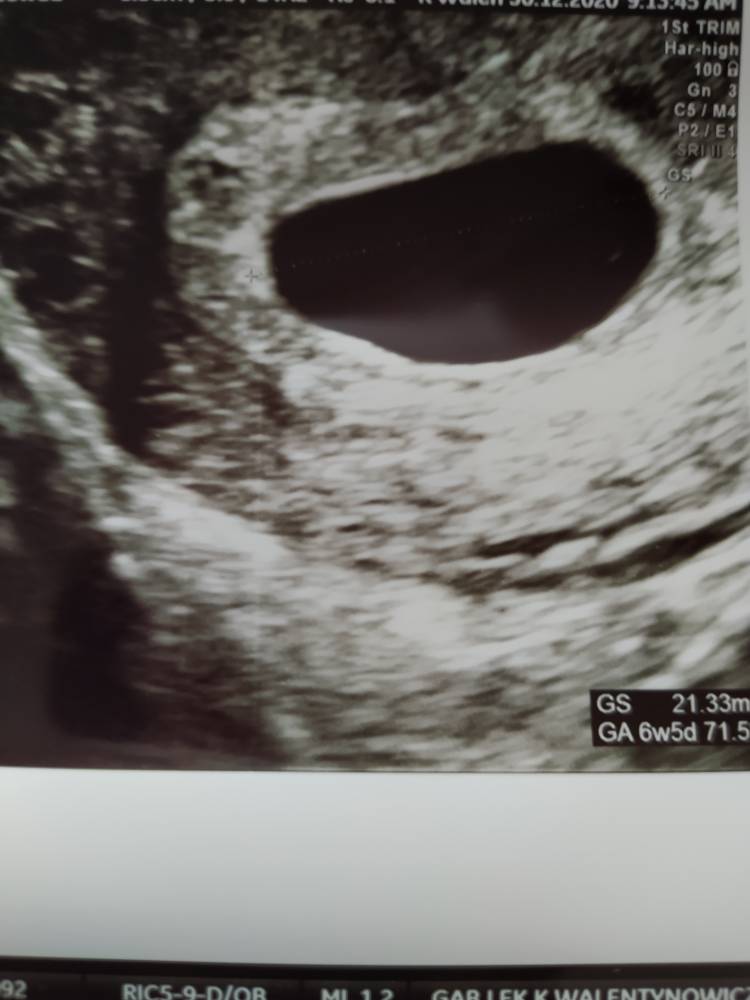

Dziś ta tragiczna wiadomość, ze jest pęcherzyk ciazowy ok. 20mm ale jest zupełnie pusty. Ani ciałka żółtego, ani zarodka. Za 5-6 dni kontrolne usg, ale skierowanie do szpitala już mam wystawione. Jestem załamana.

Czy któraś z Was to przeszła? Jaki moze być tego powód? Zachodze w ciążę za 1 podejściem. Zobacz załącznik 1221071